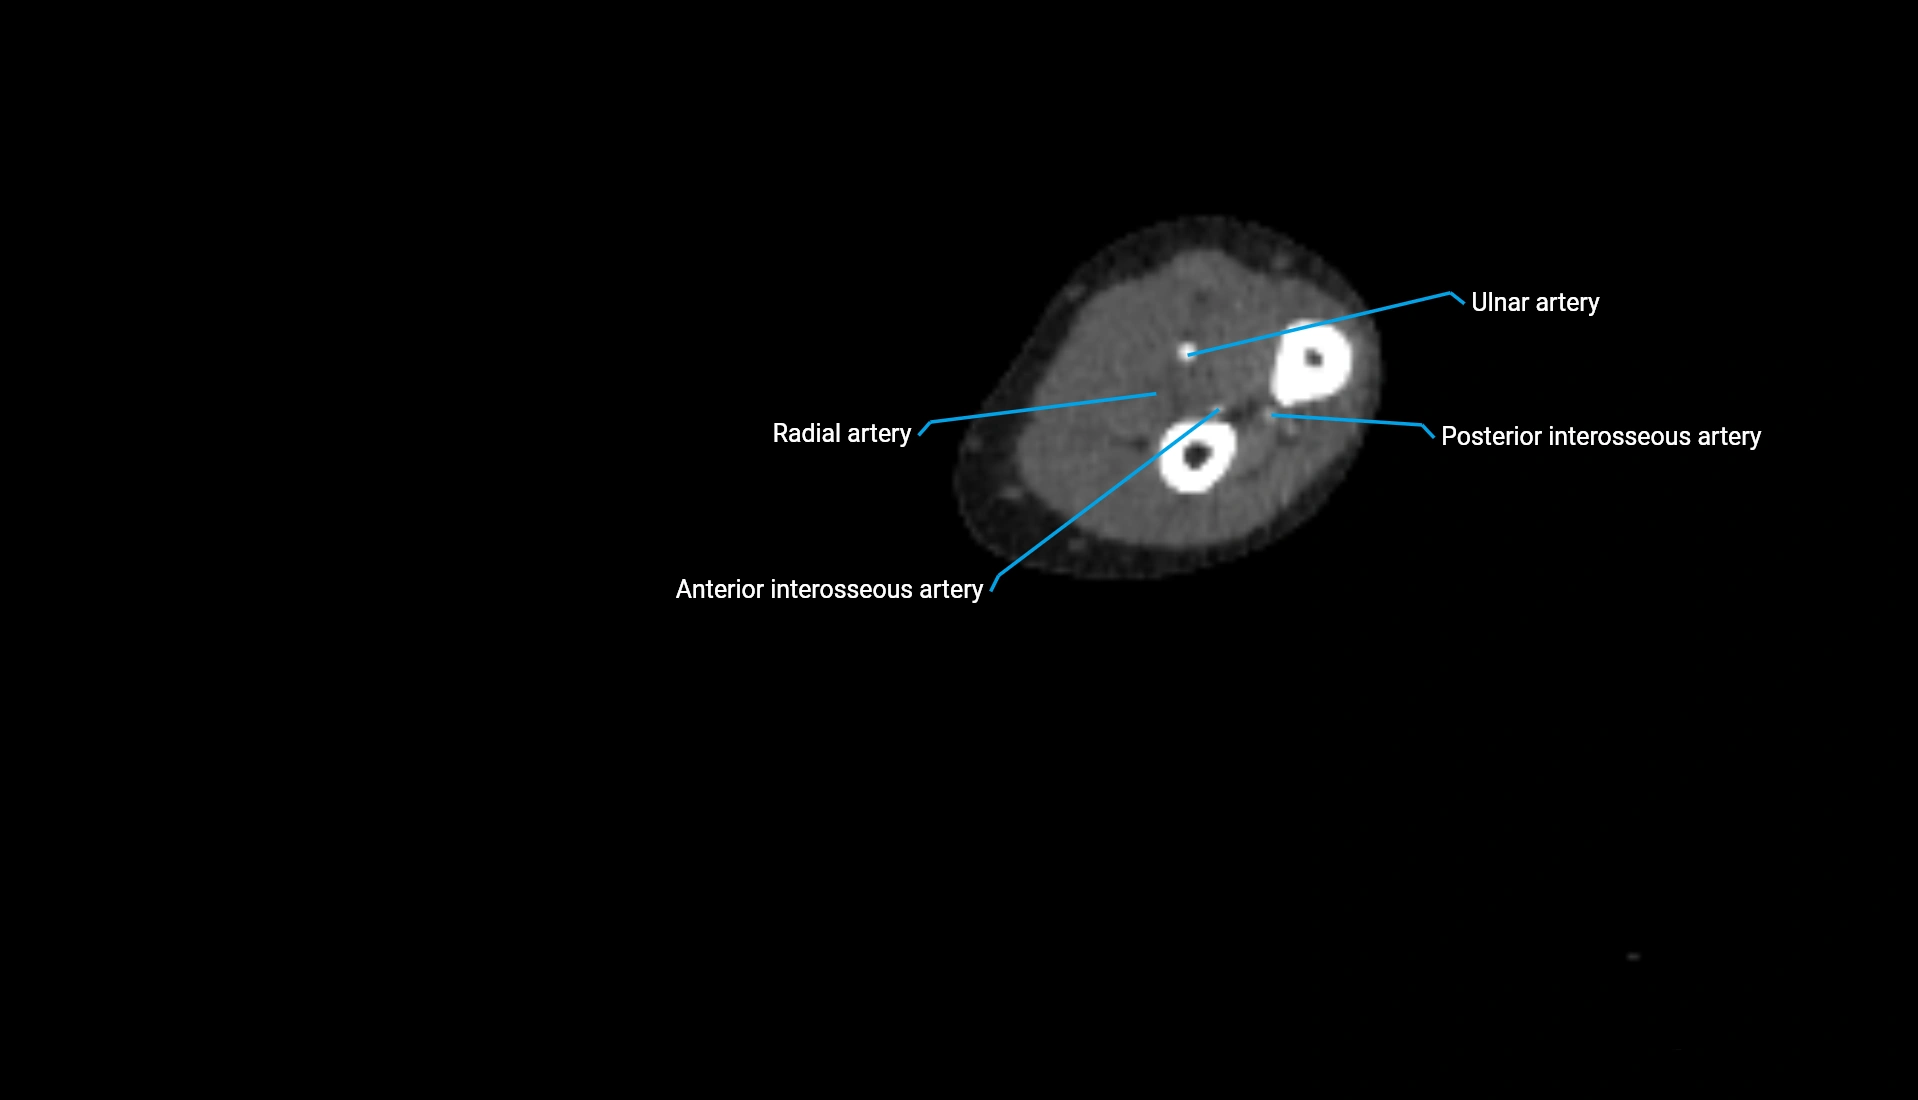

CT Appearance

Non-Contrast CT:

• Cortex: High-density, sharply defined

• Subchondral bone: Dense cancellous matrix

• Articular surface: Smooth concave contour articulating with the capitellum

• Excellent for evaluating bone integrity, alignment, and subtle fractures

Post-Contrast CT:

• Bone: No enhancement

• Joint capsule and synovium: Mild enhancement outlining the joint

• Improves contrast between soft tissues and bony margins

• Useful in detecting subtle joint abnormalities or postoperative changes